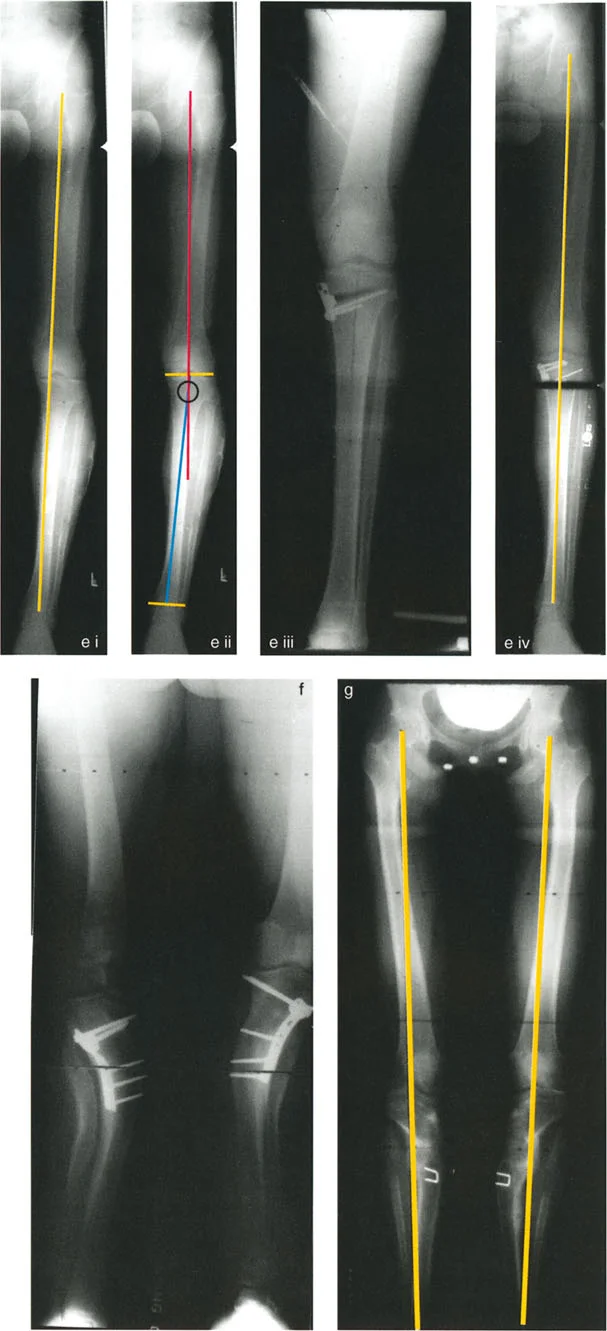

التصوير بالأشعة السينية (X-rays):

- أشعة الساق الكاملة الواقفة (Full-length Standing X-rays): هذه هي الأداة التشخيصية الأكثر أهمية لتشوهات الأطراف. يتم أخذ الصورة بينما يقف المريض، مما يسمح بتقييم المحور الميكانيكي للطرف بأكمله (من الورك إلى الكاحل) تحت تأثير تحمل الوزن. تتيح هذه الصور للجراح قياس زوايا محددة بدقة وتحديد "مركز دوران التشوه" (CORA) – وهو النقطة المحورية التي يجب أن يتم التصحيح حولها.

- أشعة مقاطع محددة: قد تكون هناك حاجة لأشعة سينية لمفاصل معينة (مثل الركبة أو الكاحل) من زوايا مختلفة لتقييم حالة المفصل والغضاريف.

أهمية التخطيط الدقيق لقطع العظم

إن نجاح جراحة تصحيح تشوهات الأطراف يعتمد بشكل كبير على التخطيط المسبق الدقيق. هذا التخطيط أشبه برسم خارطة طريق هندسية تضمن أن كل خطوة جراحية تقود إلى النتيجة المرجوة. يعتمد هذا التخطيط على "مبادئ بالي" التي تحدد ثلاثة متغيرات هندسية أساسية في كل حالة:

- مركز دوران التشوه (CORA - Center of Rotation of Angulation): هذه هي النقطة المحورية للتشوه في العظم. يحددها الجراح من خلال رسم محاور الطرف قبل الجراحة.

- محور تصحيح الزاوية (ACA - Angulation Correction Axis): هذه هي النقطة التي يدور حولها الجزء البعيد من العظم لتصحيح التشوه. يتحكم الجراح في هذه النقطة عن طريق وضع المفصلات على المثبت الخارجي أو نقطة الارتكاز للوحة التثبيت.

- مستوى قطع العظم (Osteotomy Level): هذا هو الموقع الفعلي الذي يتم فيه قطع العظم. يتحكم الجراح بشكل كامل في هذا المتغير، ويتم اختياره بناءً على عوامل مثل الأنسجة الرخوة، وجودة العظم، ونوع الأجهزة المستخدمة.

النتيجة النهائية للتصحيح تعتمد كليًا على كيفية ارتباط هذه المتغيرات الثلاثة ببعضها البعض. الفشل في التخطيط الدقيق يمكن أن يؤدي إلى "تشوهات ثانوية" غير مرغوب فيها، مثل انحراف المحور الميكانيكي أو ترجمة (إزاحة) العظم.